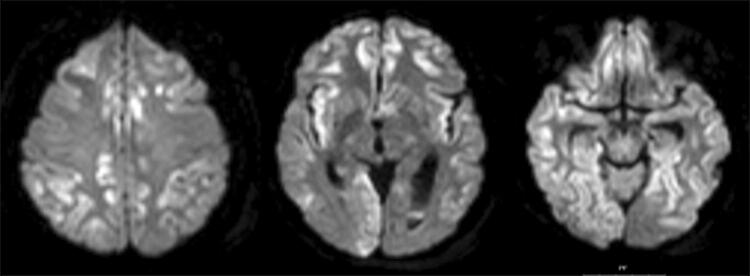

A tracheostomy was performed on day 8, and all sedatives were stopped. On day 11 a diffusion weighted MR was performed which revealed scattered bilateral cortical ischemia (Fig. 7). Electroencephalography (EEG) showed post-anoxic-ischemic alpha-coma. Nutrition was kept to a minimum of caloric intake for 5 days (10 kcal/kg/day) according to the NICE guidelines, and then increased cautiously. After two weeks eyes opened spontaneously, finger movement was present in one hand, but the patient did not obey commands or give any contact. The patient returned to the primary hospital after 15 days, was eventually admitted to a rehabilitation center, and could thereafter return to home with assistance, being able to eat and talk.

Fig. 7.

A diffusion weighted MRI on day 11 after admission showing scattered ischemic cortical lesions